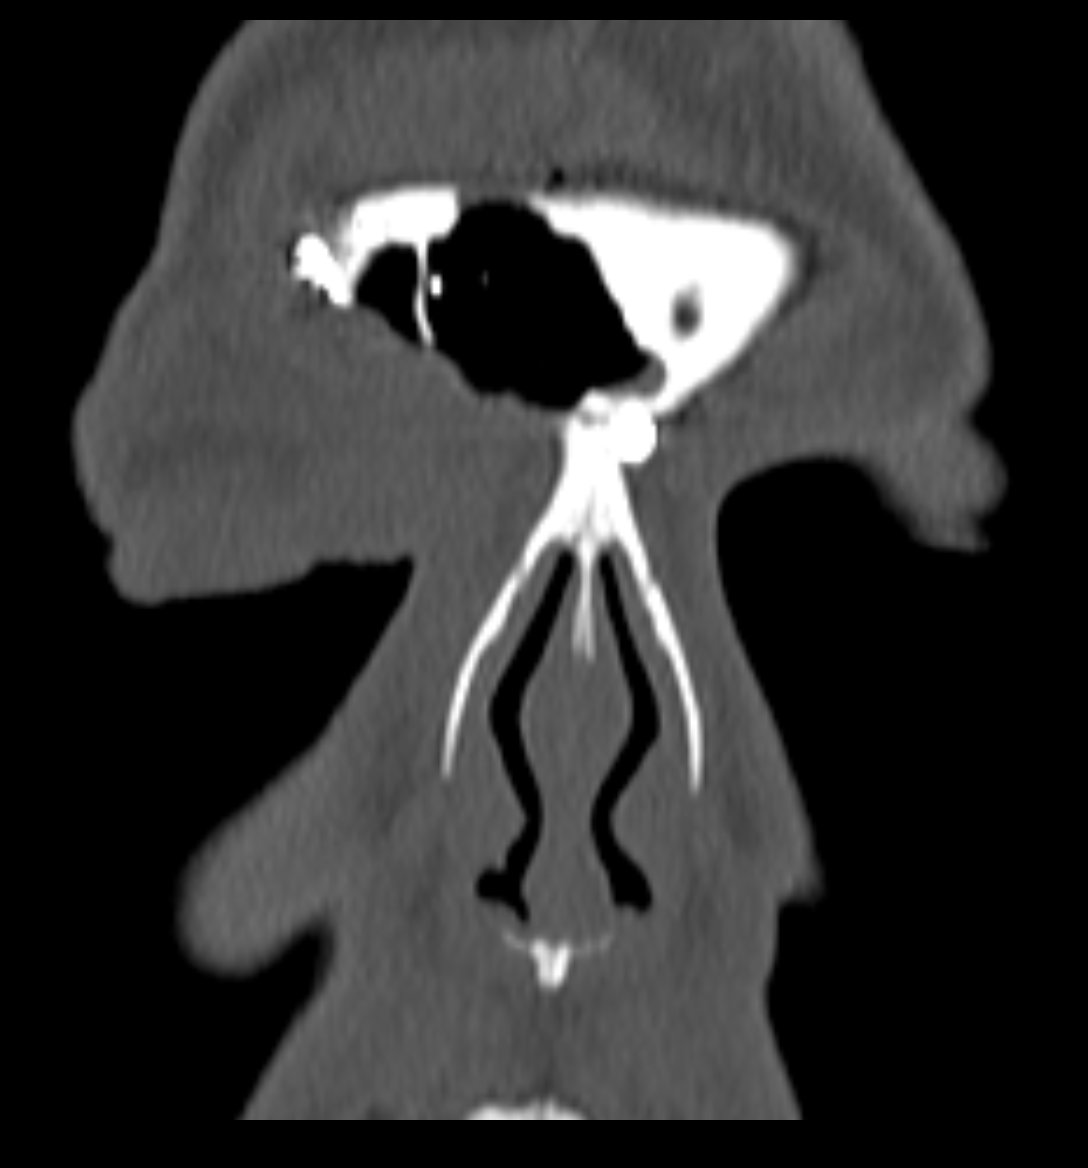

- Se expune formațiunea tumorală osteomatoasă care ocupă în totalitate cavitatea sinusală frontală dreaptă, se extinde către sinusul frontal controlateral și către orbita dreaptă, creând presiune pe atmosfera celulo-grasoasă periorbitară la nivelul unghiului supero-intern OD. Formațiunea este intens aderentă la nivelul peretelui sinusal postero-superior. Aceasta prezintă două zone de consistență diferită.

Ziua 1 postoperator, pacienta efectuează CT sinusuri paranazale de control care certifică ablația completă a formațiunii.